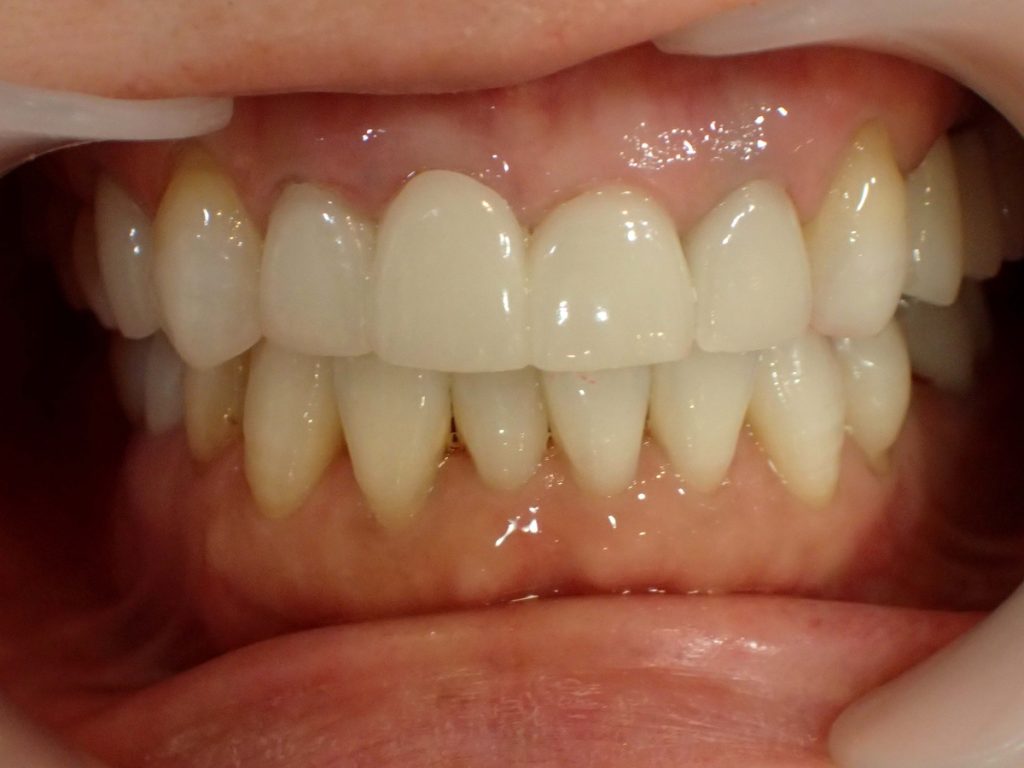

【ブラックマージン治療前】

【ブラックマージン治療後】

治療期間:1カ月半

通院回数:4回

治療内容:セラミック矯正3本

前歯3本にセラミック治療を行った方の症例です。

まわりの天然歯と比べて差し歯が黄色く変色し、歯茎部分が黒くなっていました。

セラミック治療によりまわりの歯と比べても変わらない透明感と厚みの状態にし、ブラックマージン(歯茎の黒ずみ)も改善しました。

当院では土台部分も含めて金属を一切使用しないため、時間が経って歯茎が再び黒ずむ心配がありません。